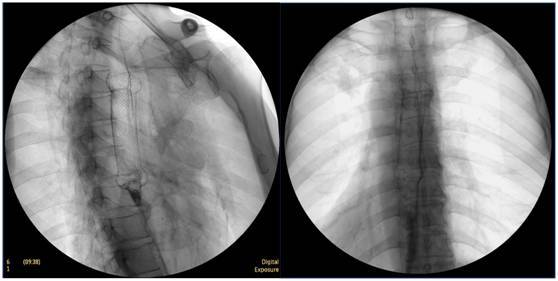

食管惡性腫瘤

食管癌并狹窄內(nèi)鏡下擴張支架植入術(shù),支架在脊柱背景下依然能清晰顯示。